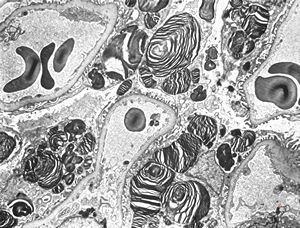

F,27y. | oncocytoma - kidney